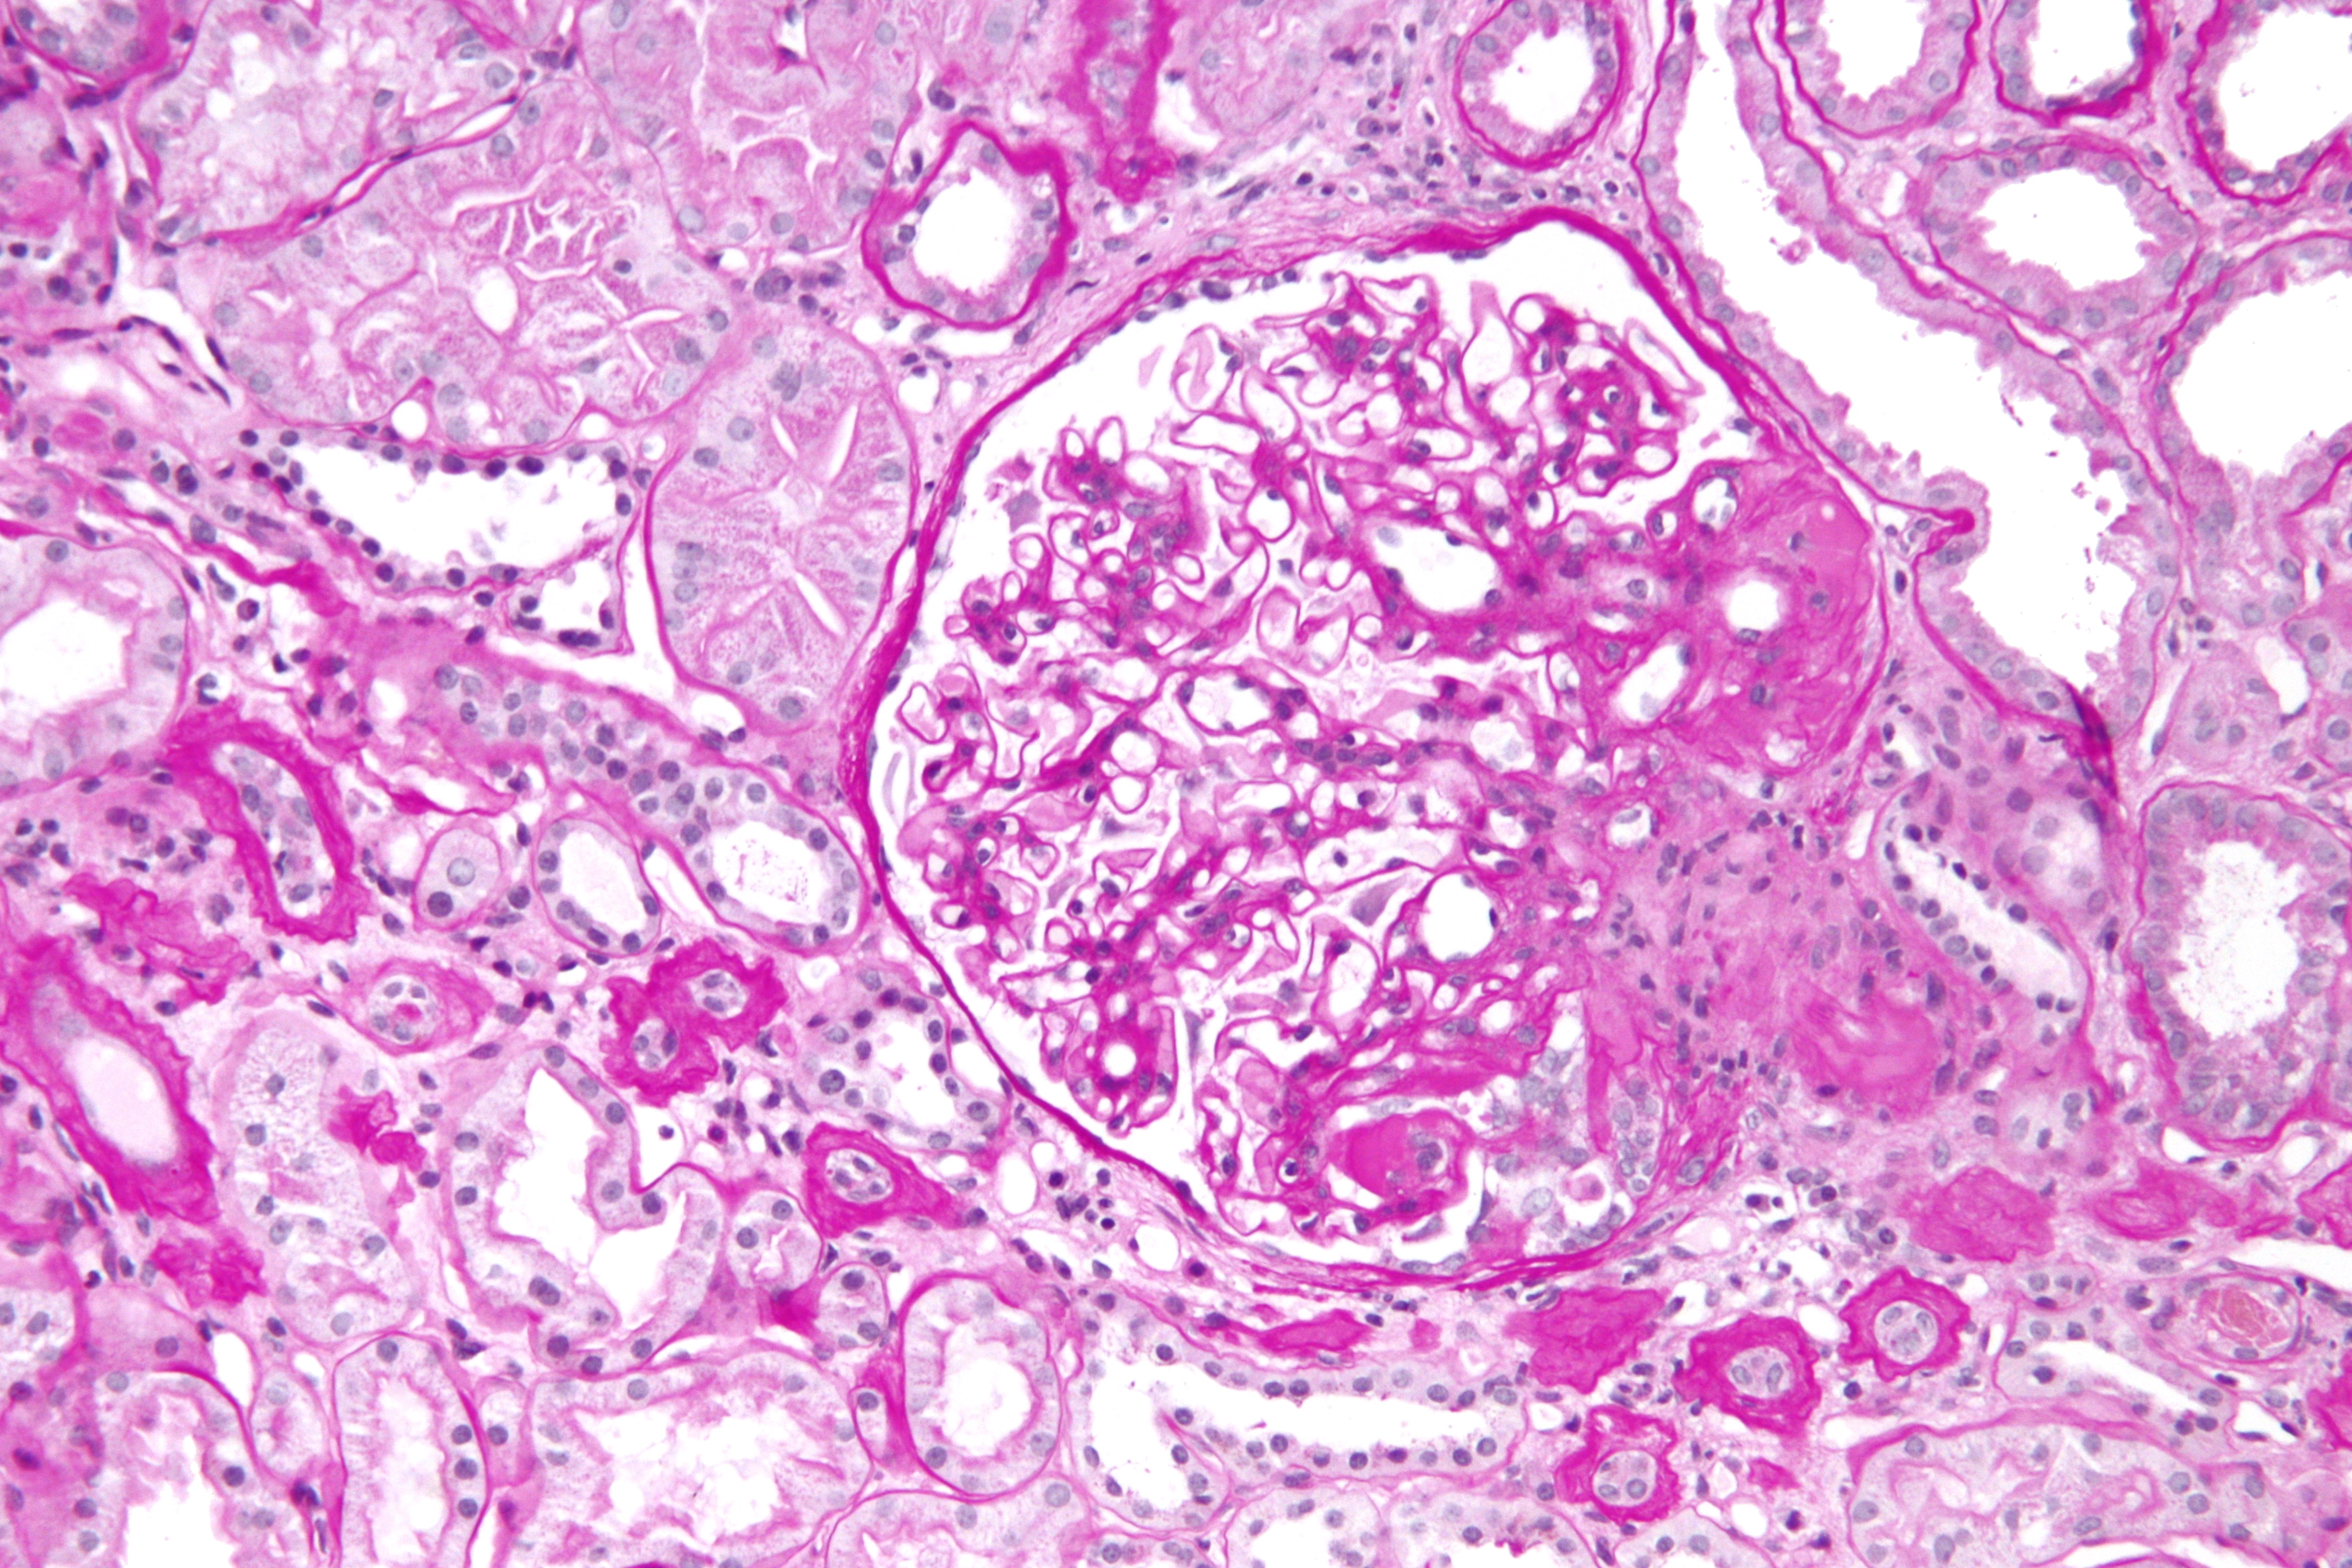

Este ensayo clínico doble ciego se comparó sparsentán, un antagonista dual de receptores de endotelina y angiotensina II, con el tratamiento estándar con irbesartán. Aunque el antagonista dual logró un mayor descenso de la proteinuria, no modificó la pendiente de descenso de la función renal al cabo de dos años de seguimiento. New England Journal of Medicine, 28 de diciembre de 2023.